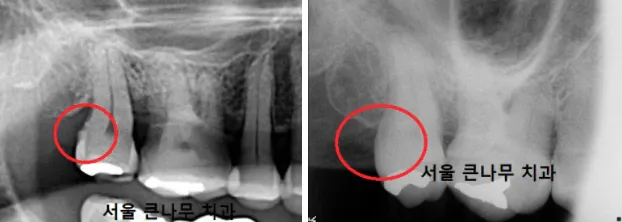

서울큰나무치과에 방문해 주신 60대 환자분입니다.

위 사진에서 보시듯이 치아 사이가 잘 닦이지 않아 전체적으로 치태와 치석이 쌓인 모습입니다.

먼저, 치석제거를 진행했습니다. 눈에 보이는 치석은 다 제거하였지만 눈에 보이지 않는 치석은 남아 있었습니다. 사진에 오돌토돌하게 남아있는 치석의 모습을 확인할 수 있었고, 잇몸치료 후 완전히 제거하였습니다.